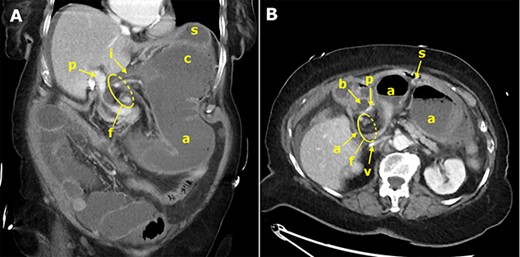

An 80-year-old patient was referred to the surgical emergency room from the internal emergency department for further therapy of abdominal pain, where the patient presented with constipation for 10 days and brownish coffee-grounds-like vomiting. At the time of presentation at the Surgical Emergency Department, the patient was already somnolent and hypotonic with a blood pressure of 90/50 mmHg, which is why further collecting of medical history was not possible. The patient was flinching during palpatory examination of the abdomen and showed signs of involuntary abdominal guarding. The laboratory blood tests at admission showed increased lactate (4.0 mmol/l) and increased inflammatory parameters such as leukocytes (50.04 · 109/l) and CRP (205.8 mg/l). The computed tomography (CT) showed a closed loop obstruction due to an internal herniation of the terminal ileum, cecum and ascending colon through the omental foramen into the lesser sac with signs of ischemic bowel injury (Fig. 1, Supplementary Video 1). The hepatoduodenal ligament was ventrally displaced with slit-like compression of the portal vein and dilation of the common bile duct. The proximal ileum loops were dilated, the downstream colon was collapsed. The clinical condition of the patient demanded an immediate transfer to the operating room. In general anesthesia, a median laparotomy was performed. After opening of the peritoneal cavity, a large hernia in the lesser sac was seen in the area of the foramen of Winslow (Fig. 2). The incarcerated right hemi-colon and about 2 m of small intestine was already necrotic due to long-term vascular occlusion. During the attempt to release the incarcerated intestines, bowel perforation occurred due to the fragility of the necrotic intestinal wall, and the intestinal content leaked to the abdominal cavity. After diligent abdominal washout procedure, a right-sided hemicolectomy and ileum partial resection with a side-to-side ileocolic anastomosis was performed. The post-operative course was without surgical complications. The patient aspirated during the initiation of anesthesia and developed pneumonia post-operatively, which needed antibiotic therapy with CPAP ventilation in the intensive care unit. This caused a transient delirious state of the patient. After psychiatric therapy adjustment and continuation of antibiotic treatment the patient’s condition improved so that the patient could be transferred to the normal ward and later on could be discharged to home care.

Contrast-enhanced CT of the abdomen; the coronal slice (A) demonstrates the terminal ileum (i), dilated cecum (c) and ascending colon (a), which are abnormally positioned upside down in the lesser sac, herniated through the omental foramen (f); the portal vein (p) is compressed; the stomach (s) is displaced ventrally and cranially; the axial slice (B) shows the ascending colon (a) exiting the hernial orifice (f), which is located between the ventrally displaced common bile duct (b) and the inferior vena cava (v).